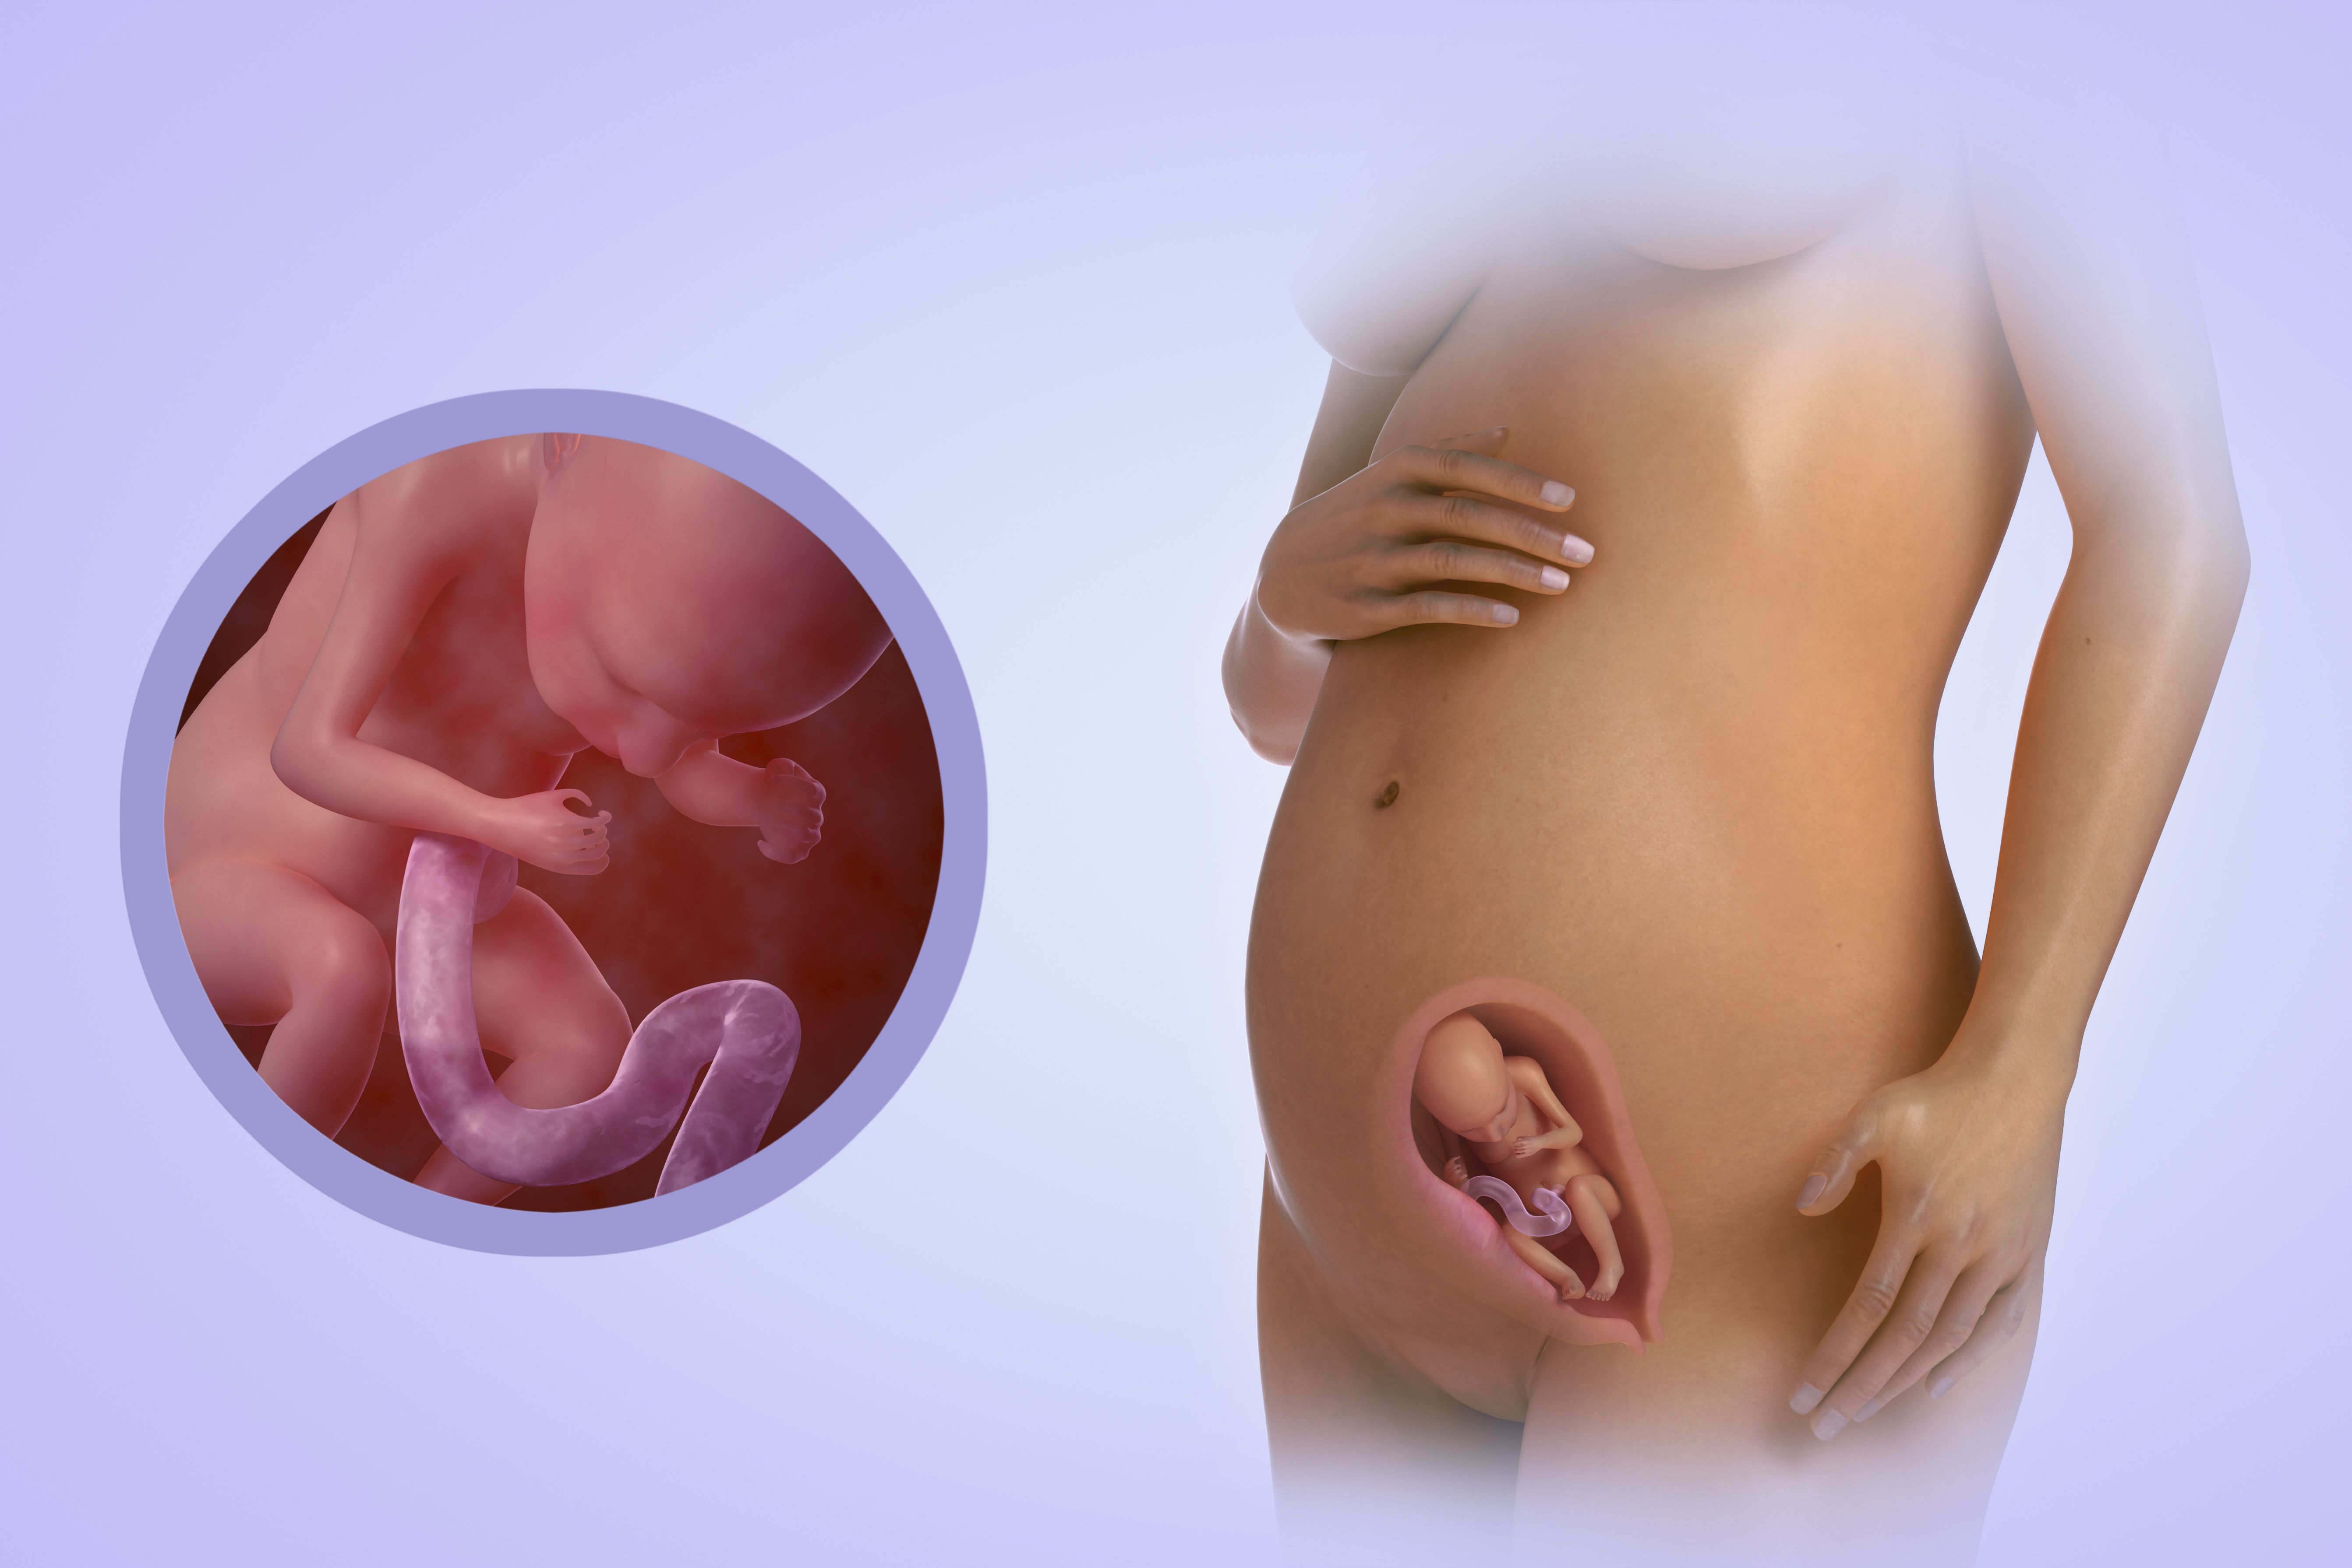

На 22 неделе беременности плод продолжает развиваться и весит уже около 450 граммов. Его длина составляет примерно 27 см. Наблюдается активное формирование мозга и нервной системы, а также развитие мышц и костей. Появляются пальчики на ногах и руках, формируются пальцы. Органы слуха продолжают развиваться, а кожа покрывается слоем мягкого волосяного покрова.

Что определяют на УЗИ

На 22-й неделе проводится второе скрининговое УЗИ, если оно не было назначено немного раньше. В отличие от первого скрининга, сейчас анализы крови не являются обязательными, если в прошлый раз не было выявлено риска рождения ребёнка с аномалиями развития. В ходе исследования врач определяет положение малыша в утробе. Оно может быть:

На 22-й неделе на УЗИ хорошо просматриваются контуры тела малыша

Оптимальным вариантом является головное предлежание, когда малыш занимает позицию головой вниз и вверх ножками. Если он сидит на попе или лежит на боку, не нужно расстраиваться, ведь ещё есть время и место в полости матки, чтобы перевернуться

Однако специалисты обращают внимание на положение плода уже сейчас. А также доктор изучает развитие жизненно важных органов, частей тела малыша, оценивает его рост и массу, соответствие гестационному сроку развития

Нормальными считаются следующие показатели:

- БПР (бипариетальный размер, измеряемый от одного до другого виска головы) – 48–60 мм;

- ОГ (окружность головы) – 64–76 мм;

- ОЖ (окружность живота) – 148–190 мм.

Оценивается также состояние матки на предмет тонуса, состояние и расположение плаценты, степень её зрелости

Немаловажное значением имеет количество околоплодных вод

На 22-й неделе на УЗИ хорошо видно, кого ждёт женщина, конечно, при условии доступного для датчика расположения половых органов плода